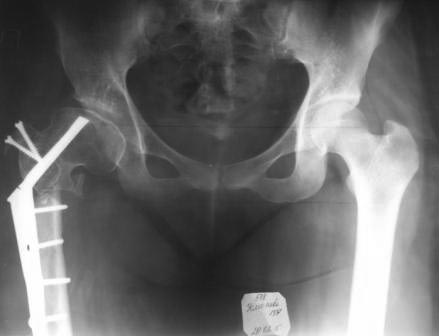

Уважаемые коллеги, обратилась девушка 1991г.р. 2 года назад

оперирована в другой области по поводу диспластического коксартроза

(похоже Мак Маррея, фиксация ЦИТО–Бакичарова), вот уже почти два года

ходит с двумя костылями, наступать на ногу не может из-за боли, ногу

активно поднять не может, активные движения в т/б суставе резко

ограничены из-за боли,  пассивные: 5/0/90гр, приведение-20,

отведение-10гр, ротация-около -30,но болезненна. Беспокоят боли в

основном в обл. ложного сустава, при движениях и пальпации в обл т/б

сустава болей нет.

На Р-грамме, похоже, клинок пластины сломан, сращения нет.